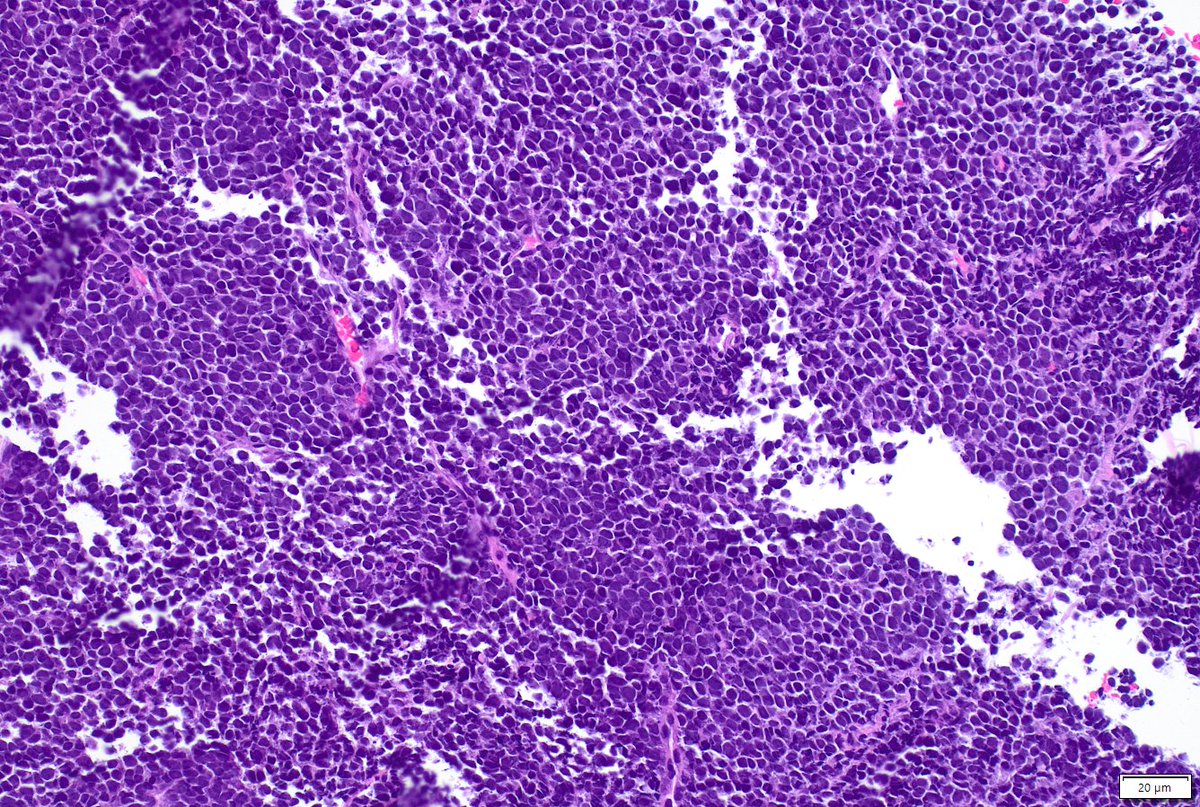

Great time showcasing our work comparing FNA vs FNB for serous cystadenomas during the Stowell-Orbinson session at #USCAP2026. Thankful for my great mentors (Dr. Centeno & Dr. Tabbara) from @MoffittNews & @USFpathology 🤩 bonus: characterizing tp53 mutations in MDS! #uscap26